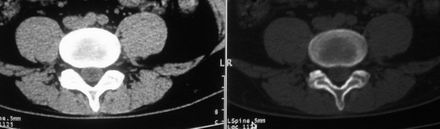

以下是引用余辉在2008-10-23 16:14:00的发言:[br]腰椎体棱角分明,小关节退变部分隔合,骶髂关节部分融合,考强脊炎